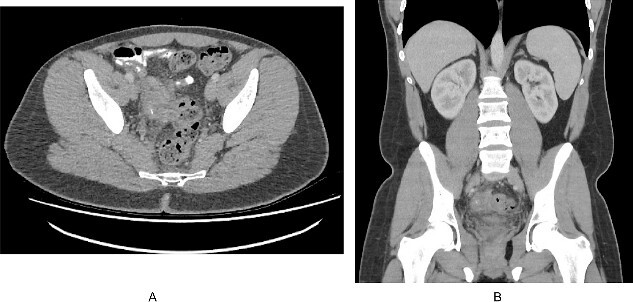

A 22 years old male with no prior medical or surgical history presented to the emergency department with 3 weeks history of lower abdominal pain and rectal discomfort. The pain was noted to be more suprapubic rather than the right iliac fossa but his abdomen was soft with no features of peritonism. He denied fevers, nausea or vomiting, or changes to bowel habits. There was no family history of bowel cancers or inflammatory bowel disease. His observations on admission were unremarkable. Pathology testing revealed a white cell count of 8.30 x 109/L and a c-reactive protein of 22 mg/L. An initial ultrasound of the abdomen visualized a non-compressible tubular structure measuring 9 mm in the right iliac fossa with 4.4 ml of surrounding free fluid and prominent lymph nodes. Given the atypical history for appendicitis, a computed tomography of the abdomen and pelvis was performed which demonstrated significant inflammatory change close to the terminal ileum extending to the right pelvic side wall with a calcific focus possibly representing an appendicolith (Fig. 1). The actual appendix was not seen as a distinct entity and the actual terminal ileum itself was not thickened.

Figure 1.

(A). Axial slice of a CT abdomen/pelvis in the portovenous phase demonstrating an inflammatory mass in the pelvis associated with the right pelvic side wall, with a calcific focus. (B). Coronal slice of the CT demonstrating the relation of the inflammatory mass within the pelvis.